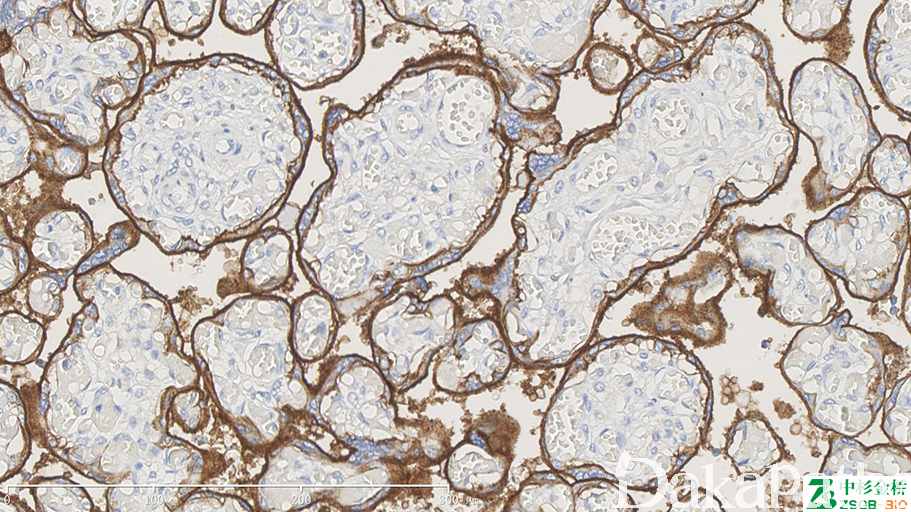

EGFR

别名: 表皮生长因子受体;HER1; c-erb-B1。

信号定位: 胞膜、胞质(少)